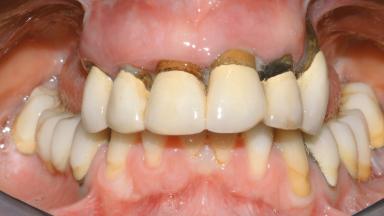

A 35-year-old Caucasian female presenting with advanced periodontal disease involving both the maxillary and the mandibular dentition was referred for evaluation. The patient, a non-smoker in good general health, requested treatment for recurrent periodontal abscesses, tooth mobility, and discomfort during chewing, as well as restoration of her missing teeth with a fixed prosthesis to improve mastication and esthetics. All residual maxillary teeth exhibited plaque deposits, deep pockets, bleeding on probing, and class III mobility and were evaluated as hopeless. All residual mandibular teeth except tooth 37 could be maintained after periodontal therapy.